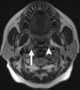

Enlarged lateral retropharyngeal lymph node